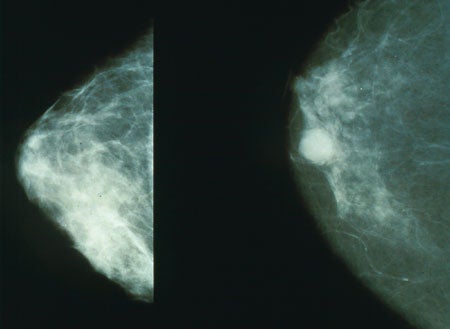

Questioning Mammograms Versus "Torturing the Data"

Another major study raises questions about the efficacy of mammography.